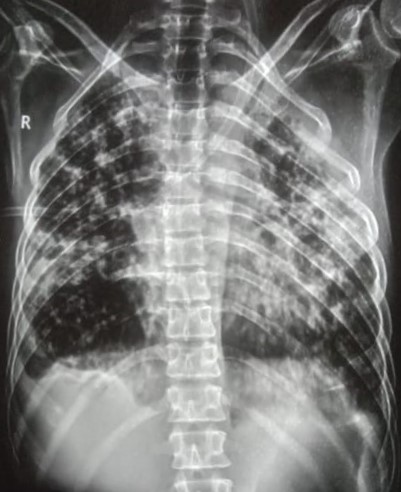

| 339 | IGGMC, Nagpur, Nagpur | P2 | 29-4133 | Narsingh Bawane | Consent taken on Paper | 32 Yrs. |

Provisional Diag : Pleural Effusion

Final Diag : Right Sided Tubercular Pleural Effusion |

TB Case (Confirmed) | Abnormality visible on x-ray |